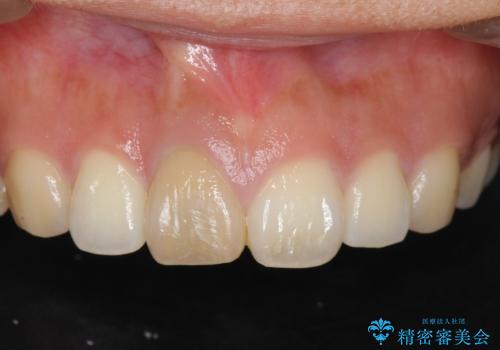

[ 再生治療・歯周外科・小矯正・セラミック補綴 ] 前歯の歯周病治療

担当医 大元洋佑